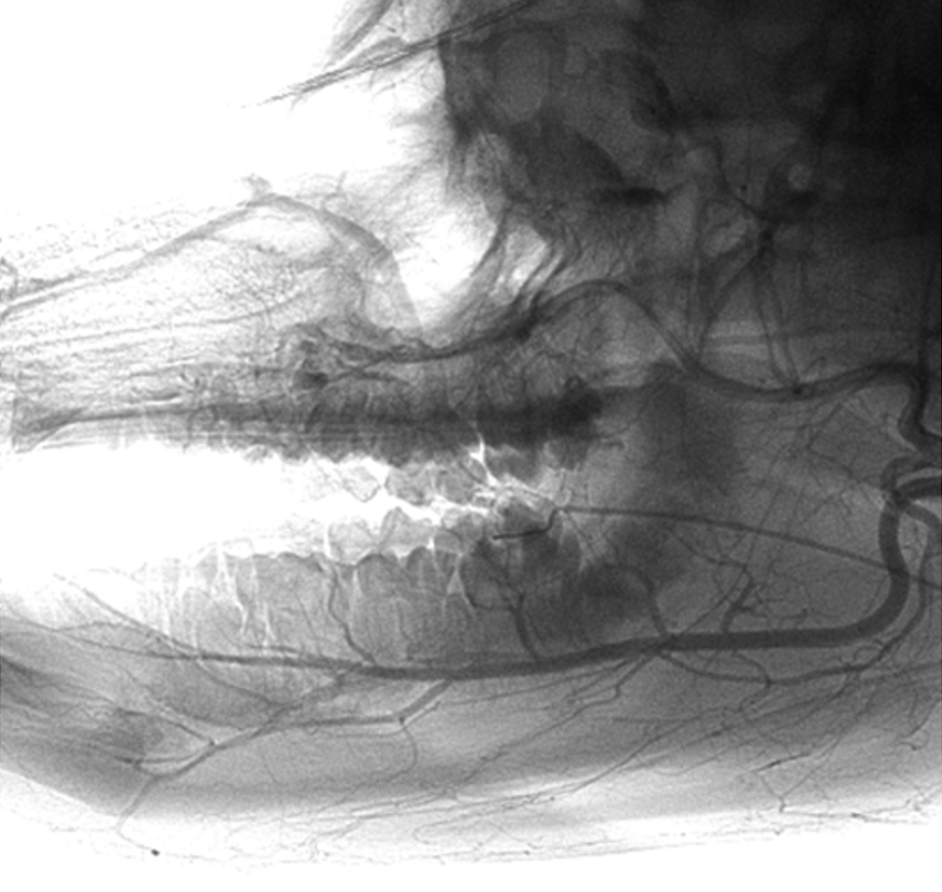

This image is an angiogram of the mandibular and maxillary vascularization in a pig!

There are important similarities between porcine and human dental vasculature, but not only: This species is also highly relevant for endovascular preclinical research. While many similarities between human and swine vasculature exist, there are important differences to consider when it comes to preclinical research. Therefore, understanding those differences is critical to guiding medical technology development and extrapolating observations in pig models to the expected safety and performance of medical devices in human patients.

This image was acquired using a Philips FD20 flat panel angiography system in one of IMMR’s two hybrid ORs that enable innovators to conduct sophisticated procedures combining surgical, interventional and imaging techniques.